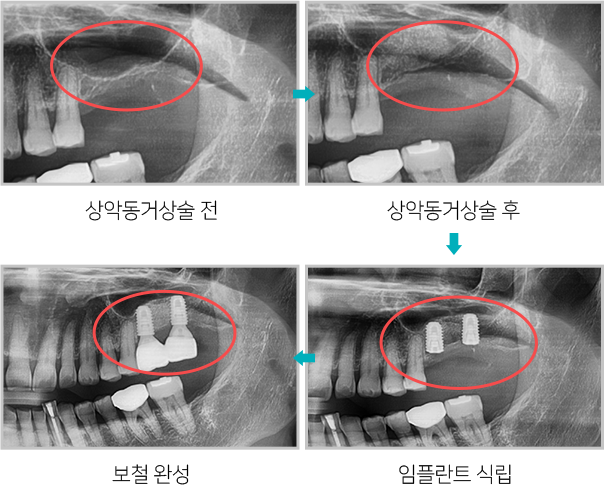

위턱뼈 속의 비어있는 공간을 상악동이라고 하는데

상악동과 잇몸뼈 사이에 임플란트를

심을 수 있는 만큼의

뼈가 남지 않았을 때, 잇몸뼈 위쪽에 위치한 상악동의

아래벽을 위쪽으로

들어올리고 그 공간에 뼈를 채워

넣어서 임플란트를 심을 수 있는 뼈의 양을

확보하는 술식입니다.

상악동거상술 전후

상악동거상술 모식도